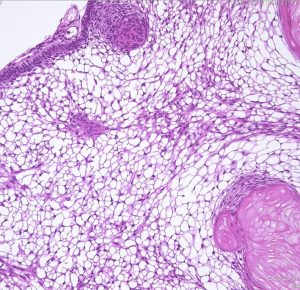

成人の第3脳室内部に局在する頭蓋咽頭腫です。経脳梁法で両側のモンロー孔から全摘出しました。下垂体組織は残っています。これは乳頭状頭蓋咽頭腫と呼ばれるもので,成人にしか発生しません,のう胞がなく石灰化もないのが大きな特徴です。境界が明瞭で柔らかく摘出が簡単なタイプとして知られています。この患者さんも術後に下垂体機能不全も視床下部障害も生じませんでした。

Monomorphous mass of well-differenciated squamous epithelium lacking surface maturation and wet keratin.